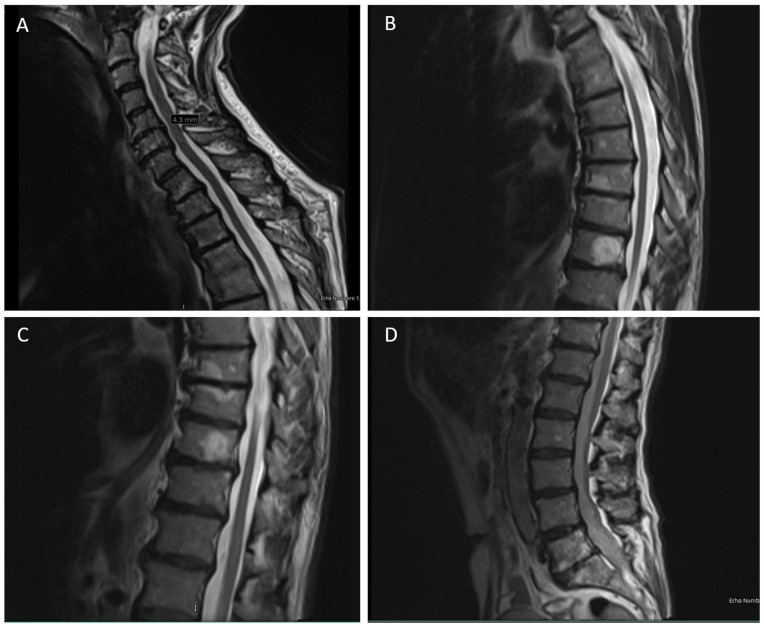

The diverse group of neurodegenerative disorders known as hereditary spastic paraplegia (HSP) is characterized by spasticity and weakness of the bilateral lower extremity due to degeneration of the corticospinal tract. The pathogenesis of HSP is broad, with autosomal dominant, autosomal recessive, X-linked recessive, mitochondrial inheritance, and de novo mutations reported, along with remarkable heterogeneity of mutations and clinical presentation. Of these, the most common subtype of HSP is HSP type 4 (HSP-SPG4), a result of mutations in the SPAST gene (chromosome 2p22.3) that leads to impaired activity of the microtubule-severing protein spastin. Typically presenting as an uncomplicated, autosomal dominant form of the disease, HSP-SPG4 has been documented worldwide with vast genomic variance across the SPAST gene. Despite common features in clinical phenotypes, a clear link between SPAST gene variants and disease presentation remains vague. Here, we report a novel 26.1 kb deletion in the SPAST gene (del exons 4-7) in a US family with previously undiagnosed HSP-SPG4.